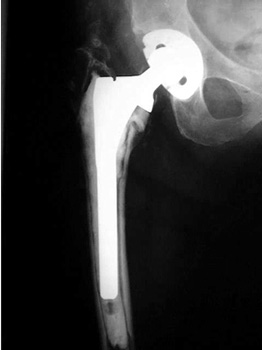

SUBSIDENCE - loose femoral prosthesis with interface widening,

osteolysis Gruen zone 6, cement fracture left femoral component

and osteolysis, with femoral component in valgus.